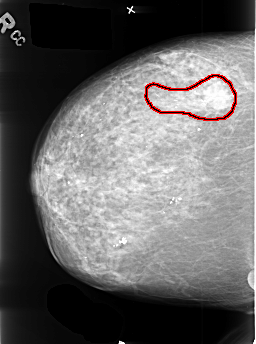

B_3411_1.RIGHT_CC

RIGHT_CC LINES 4464 PIXELS_PER_LINE 3320 BITS_PER_PIXEL 12 RESOLUTION 50 OVERLAY

FILE: B_3411_1.RIGHT_CC.OVERLAY

TOTAL_ABNORMALITIES 1

ABNORMALITY 1

LESION_TYPE CALCIFICATION TYPE N/A DISTRIBUTION LINEAR

LESION_TYPE MASS SHAPE IRREGULAR MARGINS ILL_DEFINED-SPICULATED

ASSESSMENT 5

SUBTLETY 5

PATHOLOGY MALIGNANT

TOTAL_OUTLINES 1

BOUNDARY